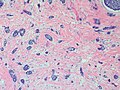

Adenoid cystic carcinoma of the breast

Adenoid cystic carcinoma of the breast. H&E stain. | |

Adenoid cystic carcinoma of the breast is a rare type of breast cancer that is similar to a relatively common tumour of the salivary gland.

Microscopic